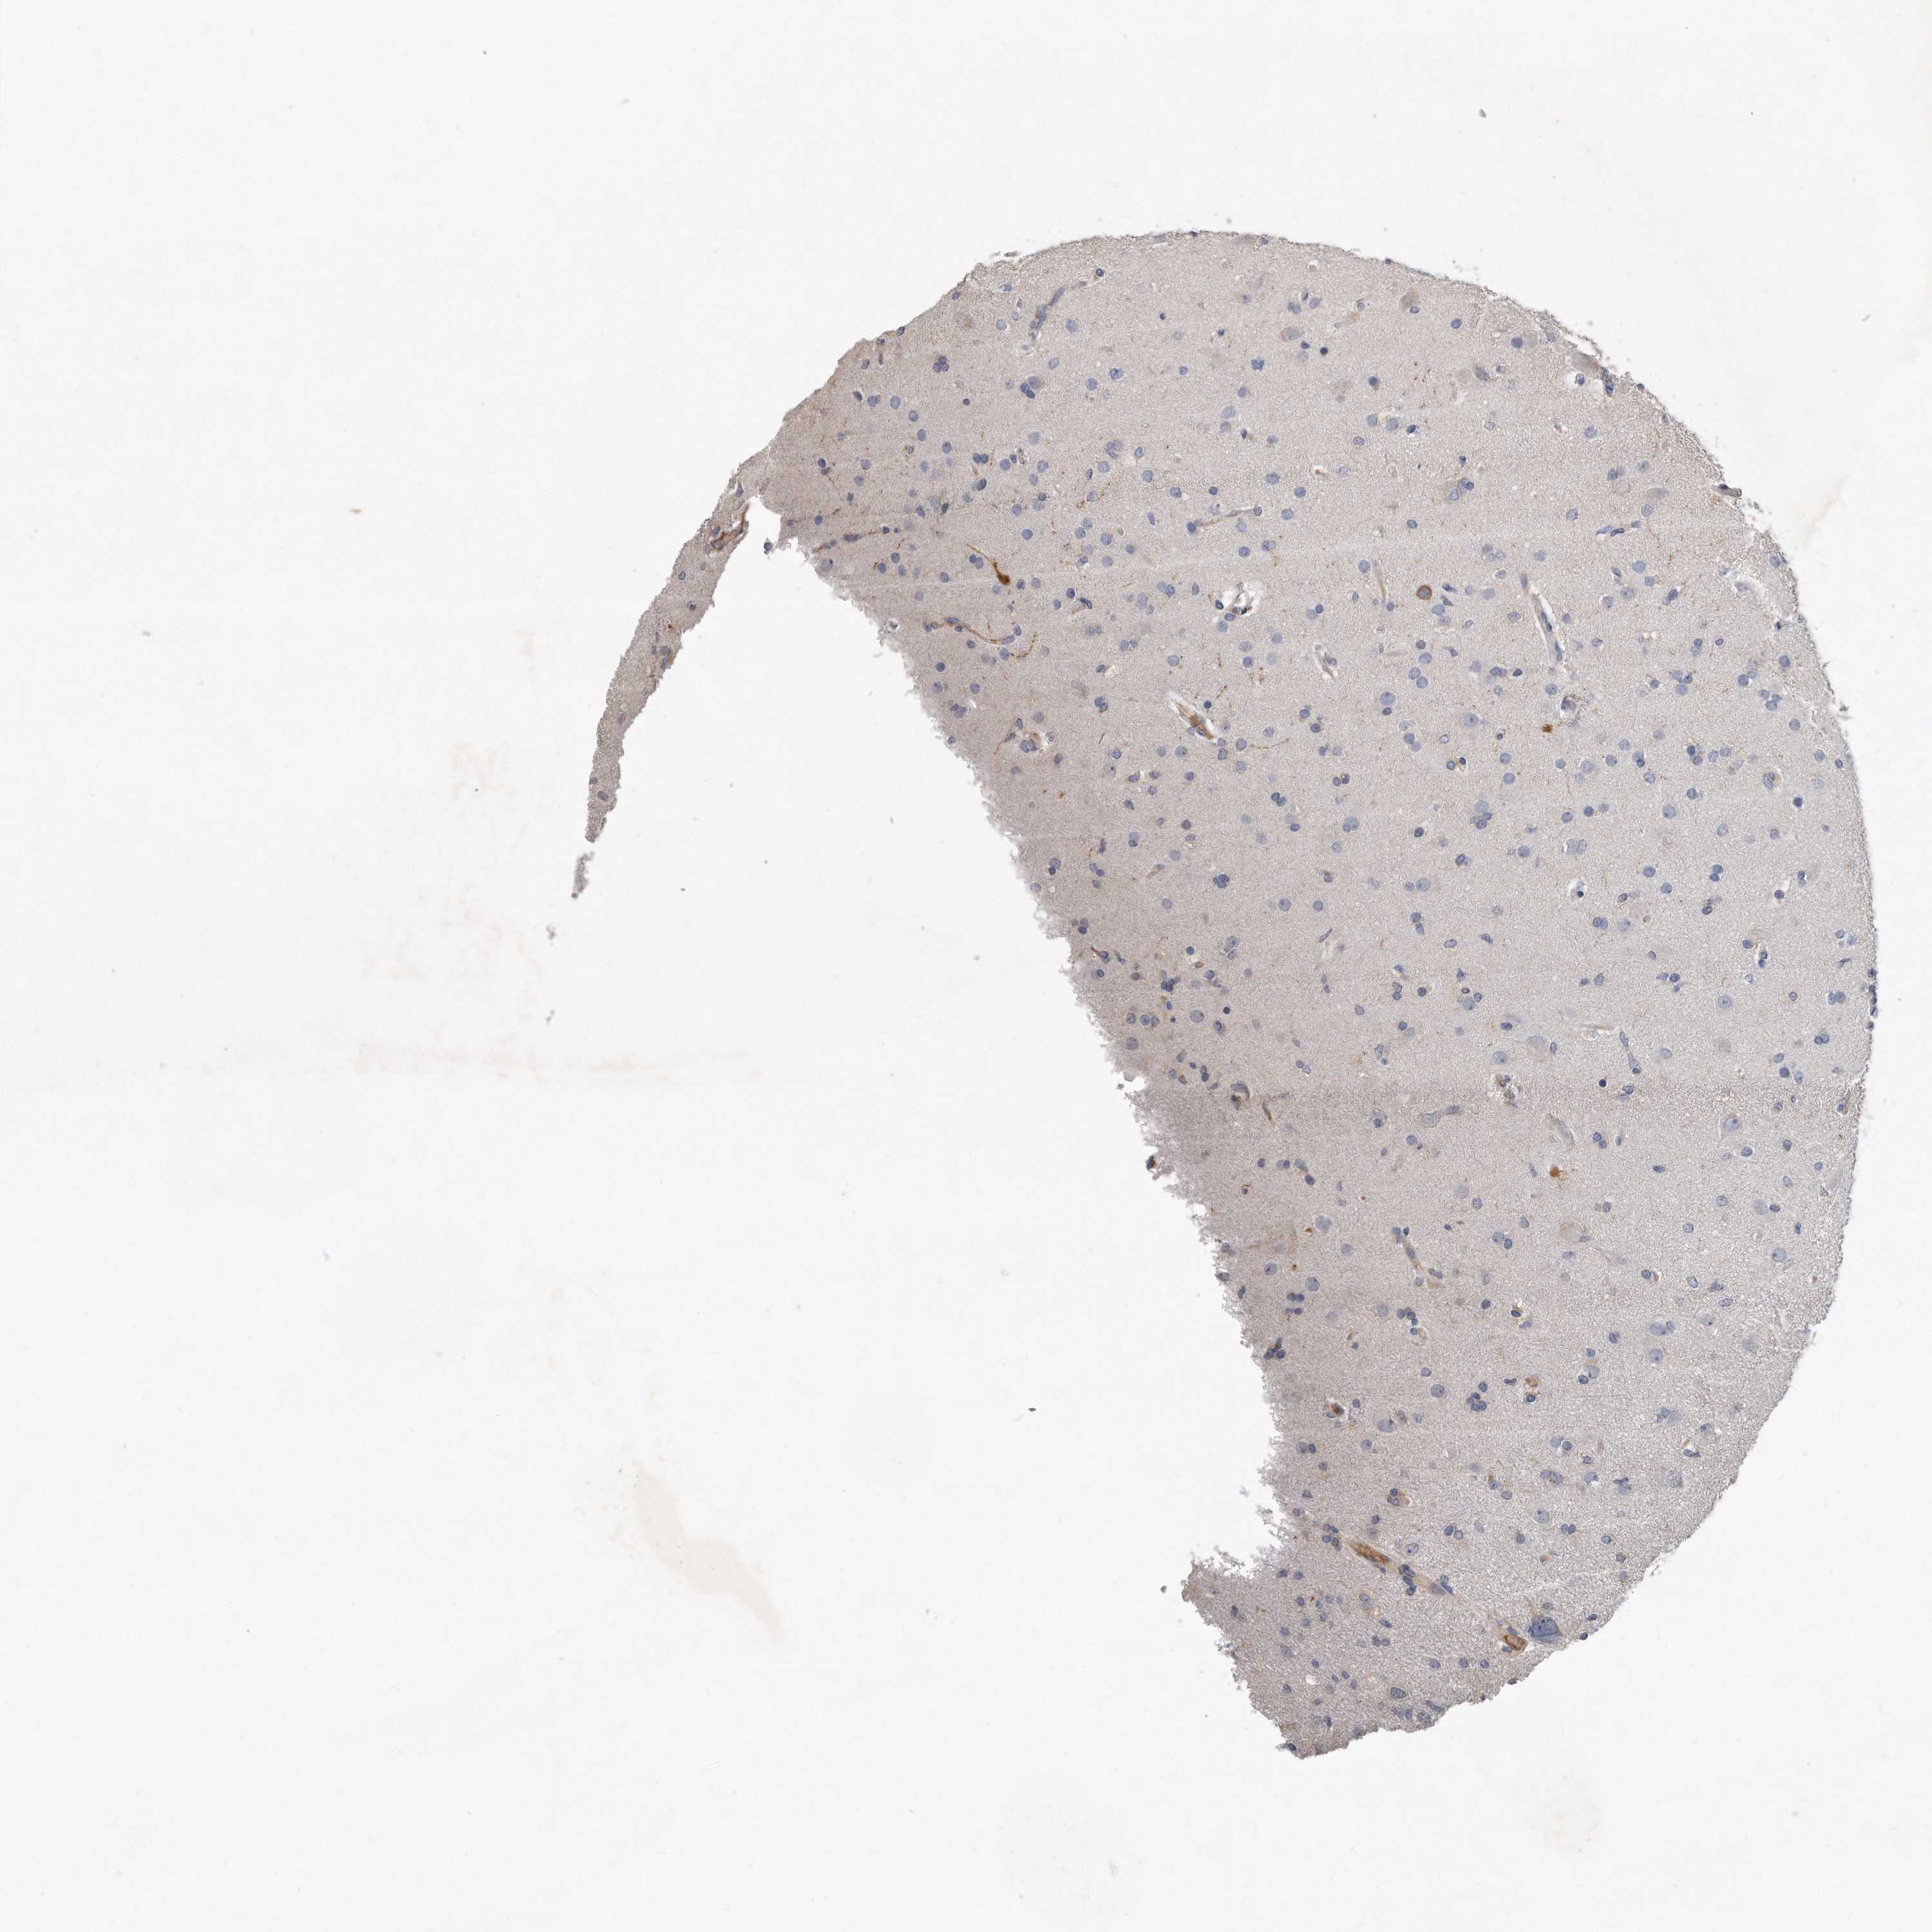

GLIOMA - Protein expressioni

A mouse-over function shows sample information and annotation data. Click on an image to view it in a full screen mode. Samples can be filtered based on level of antibody staining by selecting one or several of the following categories: high, medium, low and not detected. The assay and annotation is described here.

Note that samples used for immunohistochemistry by the Human Protein Atlas do not correspond to samples in the TCGA dataset.

Antibody stainingi

Antibody staining in the annotated cell types in the current human tissue is reported as not detected, low, medium, or high, based on conventional immunohistochemistry profiling in selected tissues. This score is based on the combination of the staining intensity and fraction of stained cells.

Each image is clickable and will lead to virtual microscopy that enables deeper exploration of all samples and also displays staining intensity scores, fraction scores and subcellular localization as well as patient and tissue information for each sample.

Antibody HPA040999

Antibody CAB032656

Staining

High

Medium

Low

Not detected

Intensity

Strong

Moderate

Weak

Negative

Quantity

>75%

75%-25%

<25%

None

Location

Nuclear

Cytoplasmic/membranous

Cytoplasmic/membranous,nuclear

Glioma, malignant, High grade

Glioma, malignant, Low grade